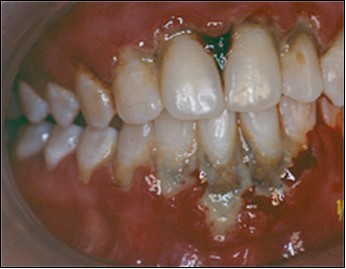

The use of the subepithelial connective tissue graft offers a combination of both the pedicle flap and the free gingival graft. The pedicle flap allows for possible root coverage since it retains its apical blood supply and therefore survives over an avascular root surface5. The free gingival graft supplies a resilient type of connective tissue with a genetic predisposition which ensures thickness and keratinization (Karring and Löe4. The double-blood supply, that from the underlying periosteum and the overlying flap, seems to be enough to nourish the entire graft5. Regarding the effect of the Er:YAG laser for periodontal treatment, its has been advocated because of its potential to decontaminate the diseased root surface and the periodontal pocket7. It may also help to remove the adjacent pocket epithelium and the calculus from root surfaces6,3. Cobbe et al2 and Ando et al1, examined in vivo bactericidal effect and conclude that the exposure of the root surface to laser could significantly decrease the levels of subgingival Actinobacillus actinomycetemcomitans, Porphyromonas gingivalis and Prevotella intermedia. In this study the Er:YAG laser was applied at powers ranging from 25 to 100 mJ/ pulse / sec. The laser irradiation was performed under water irrigation, with the tip held perpendicular to the exposed root to promote decontamination of root surface and try to remove the smear layer produced by instrumentation. The laser was also applied on the free gingival graft to remove keratinized epithelium from connective tissue graft. Those procedures seem to be efficient, although histology is not available at this time. However ours clinical results after 2 years have maintained a stable position (Figure 8).